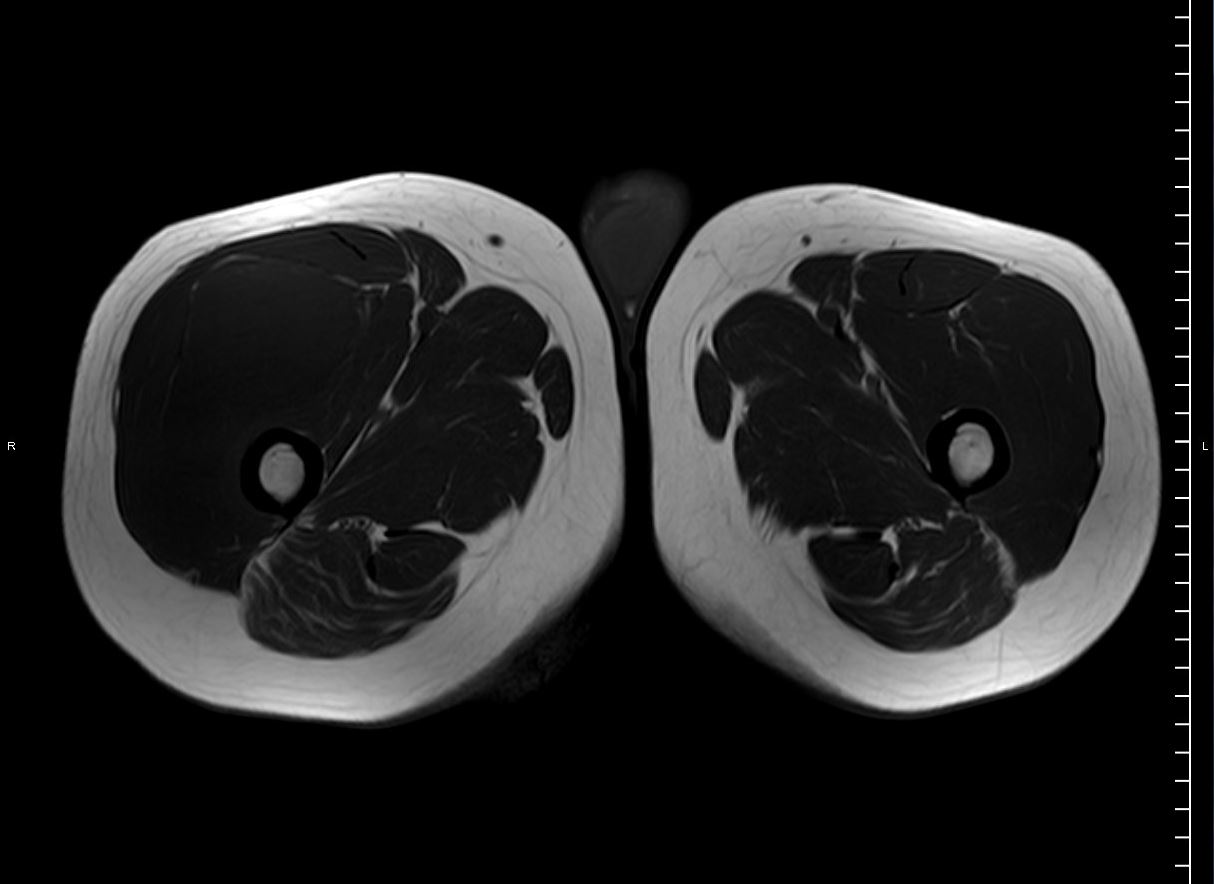

RM t2 axial

HALLAZGOS RADIOLÓGICOS